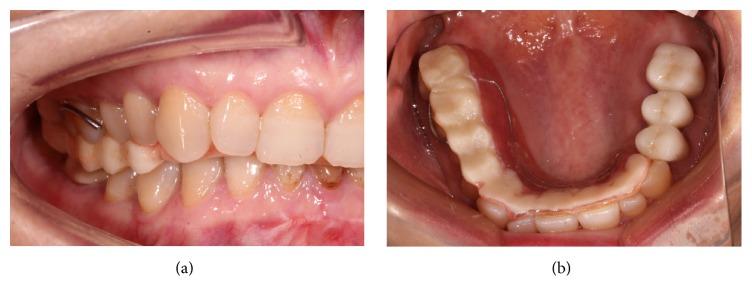

重度磨损牙合并前牙深覆(牙合)的固定修复方案

Full mouth reconstruction is one of the most effective methods to restore severe worn teeth that have suffered reduced vertical dimension. Although the use of the overlay splint restoration for a trial period allowing the patient to adapt to an increased vertical dimension is the recognized method, the specific protocol from the transitional splint to the fixed reconstruction is yet to be established. This case report describes a 50-year-old female patient who has severely worn teeth combined with an anterior deep bite and chewing pain. The protocol of the treatment process is described.

全口重建是恢复垂直距离降低的严重磨损牙齿的最有效方法之一。尽管使用覆盖式夹板修复进行一段时间的试验,让患者适应增加的垂直距离是公认的方法,但从过渡性夹板到固定重建的具体方案尚未确立。本病例报告描述了一名50岁女性患者,其牙齿严重磨损,伴有前牙深覆合和咀嚼疼痛。文中描述了治疗过程的方案。